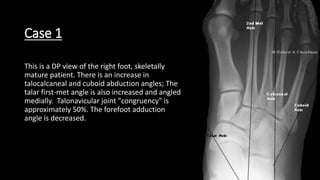

This is a DP view of the right foot, skeletally

mature patient. There is an increase in

talocalcaneal and cuboid abduction angles; The

talar first-met angle is also increased and angled

medially. Talonavicular joint "congruency" is

approximately 50%. The forefoot adduction

angle is decreased.